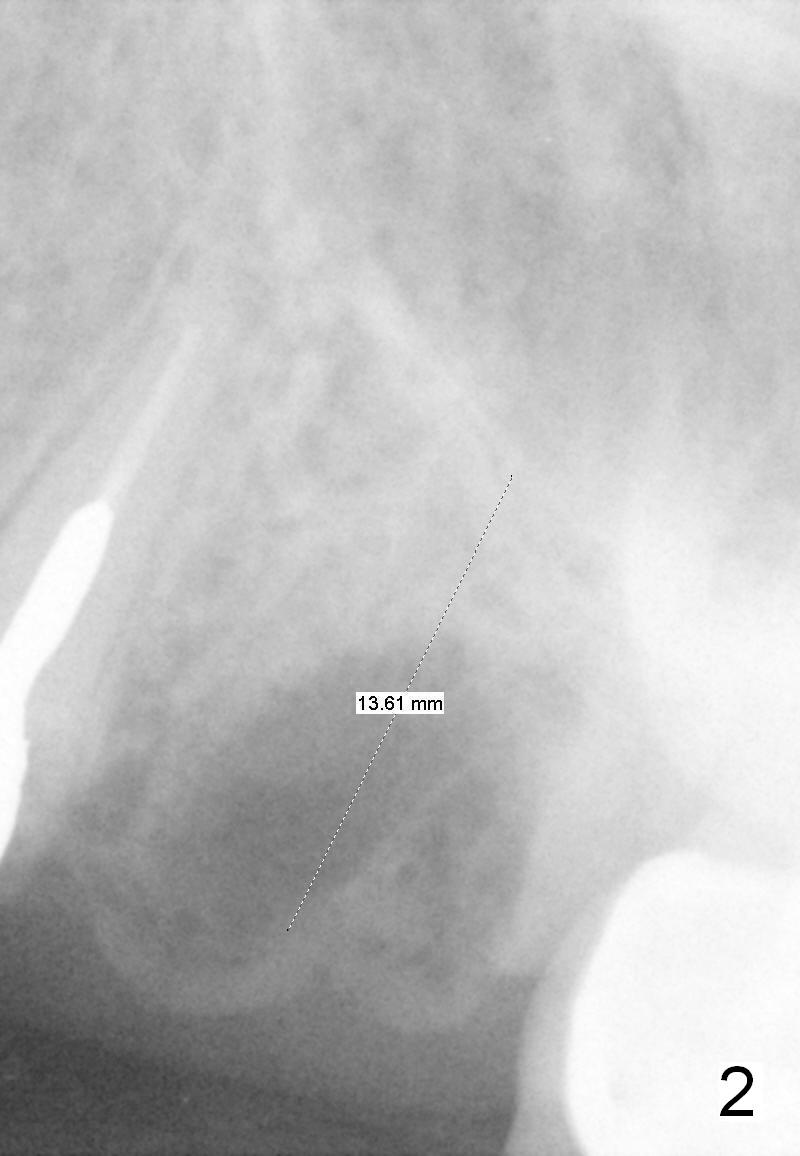

A 58-year-old white woman is afraid of dentistry (Fig1). Two years post extraction of the tooth #14, the bone height reduces by 4 mm (compare Fig.2,3).